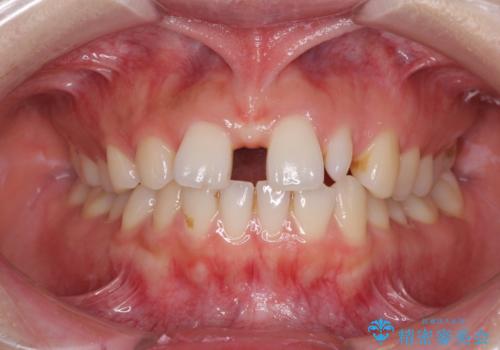

前歯を整えたい 小さい前歯がある 矯正・セラミック併用で美しく インビザラインでも抜歯矯正できます

欠損歯と矮小歯 矯正治療と前歯のセラミック治療